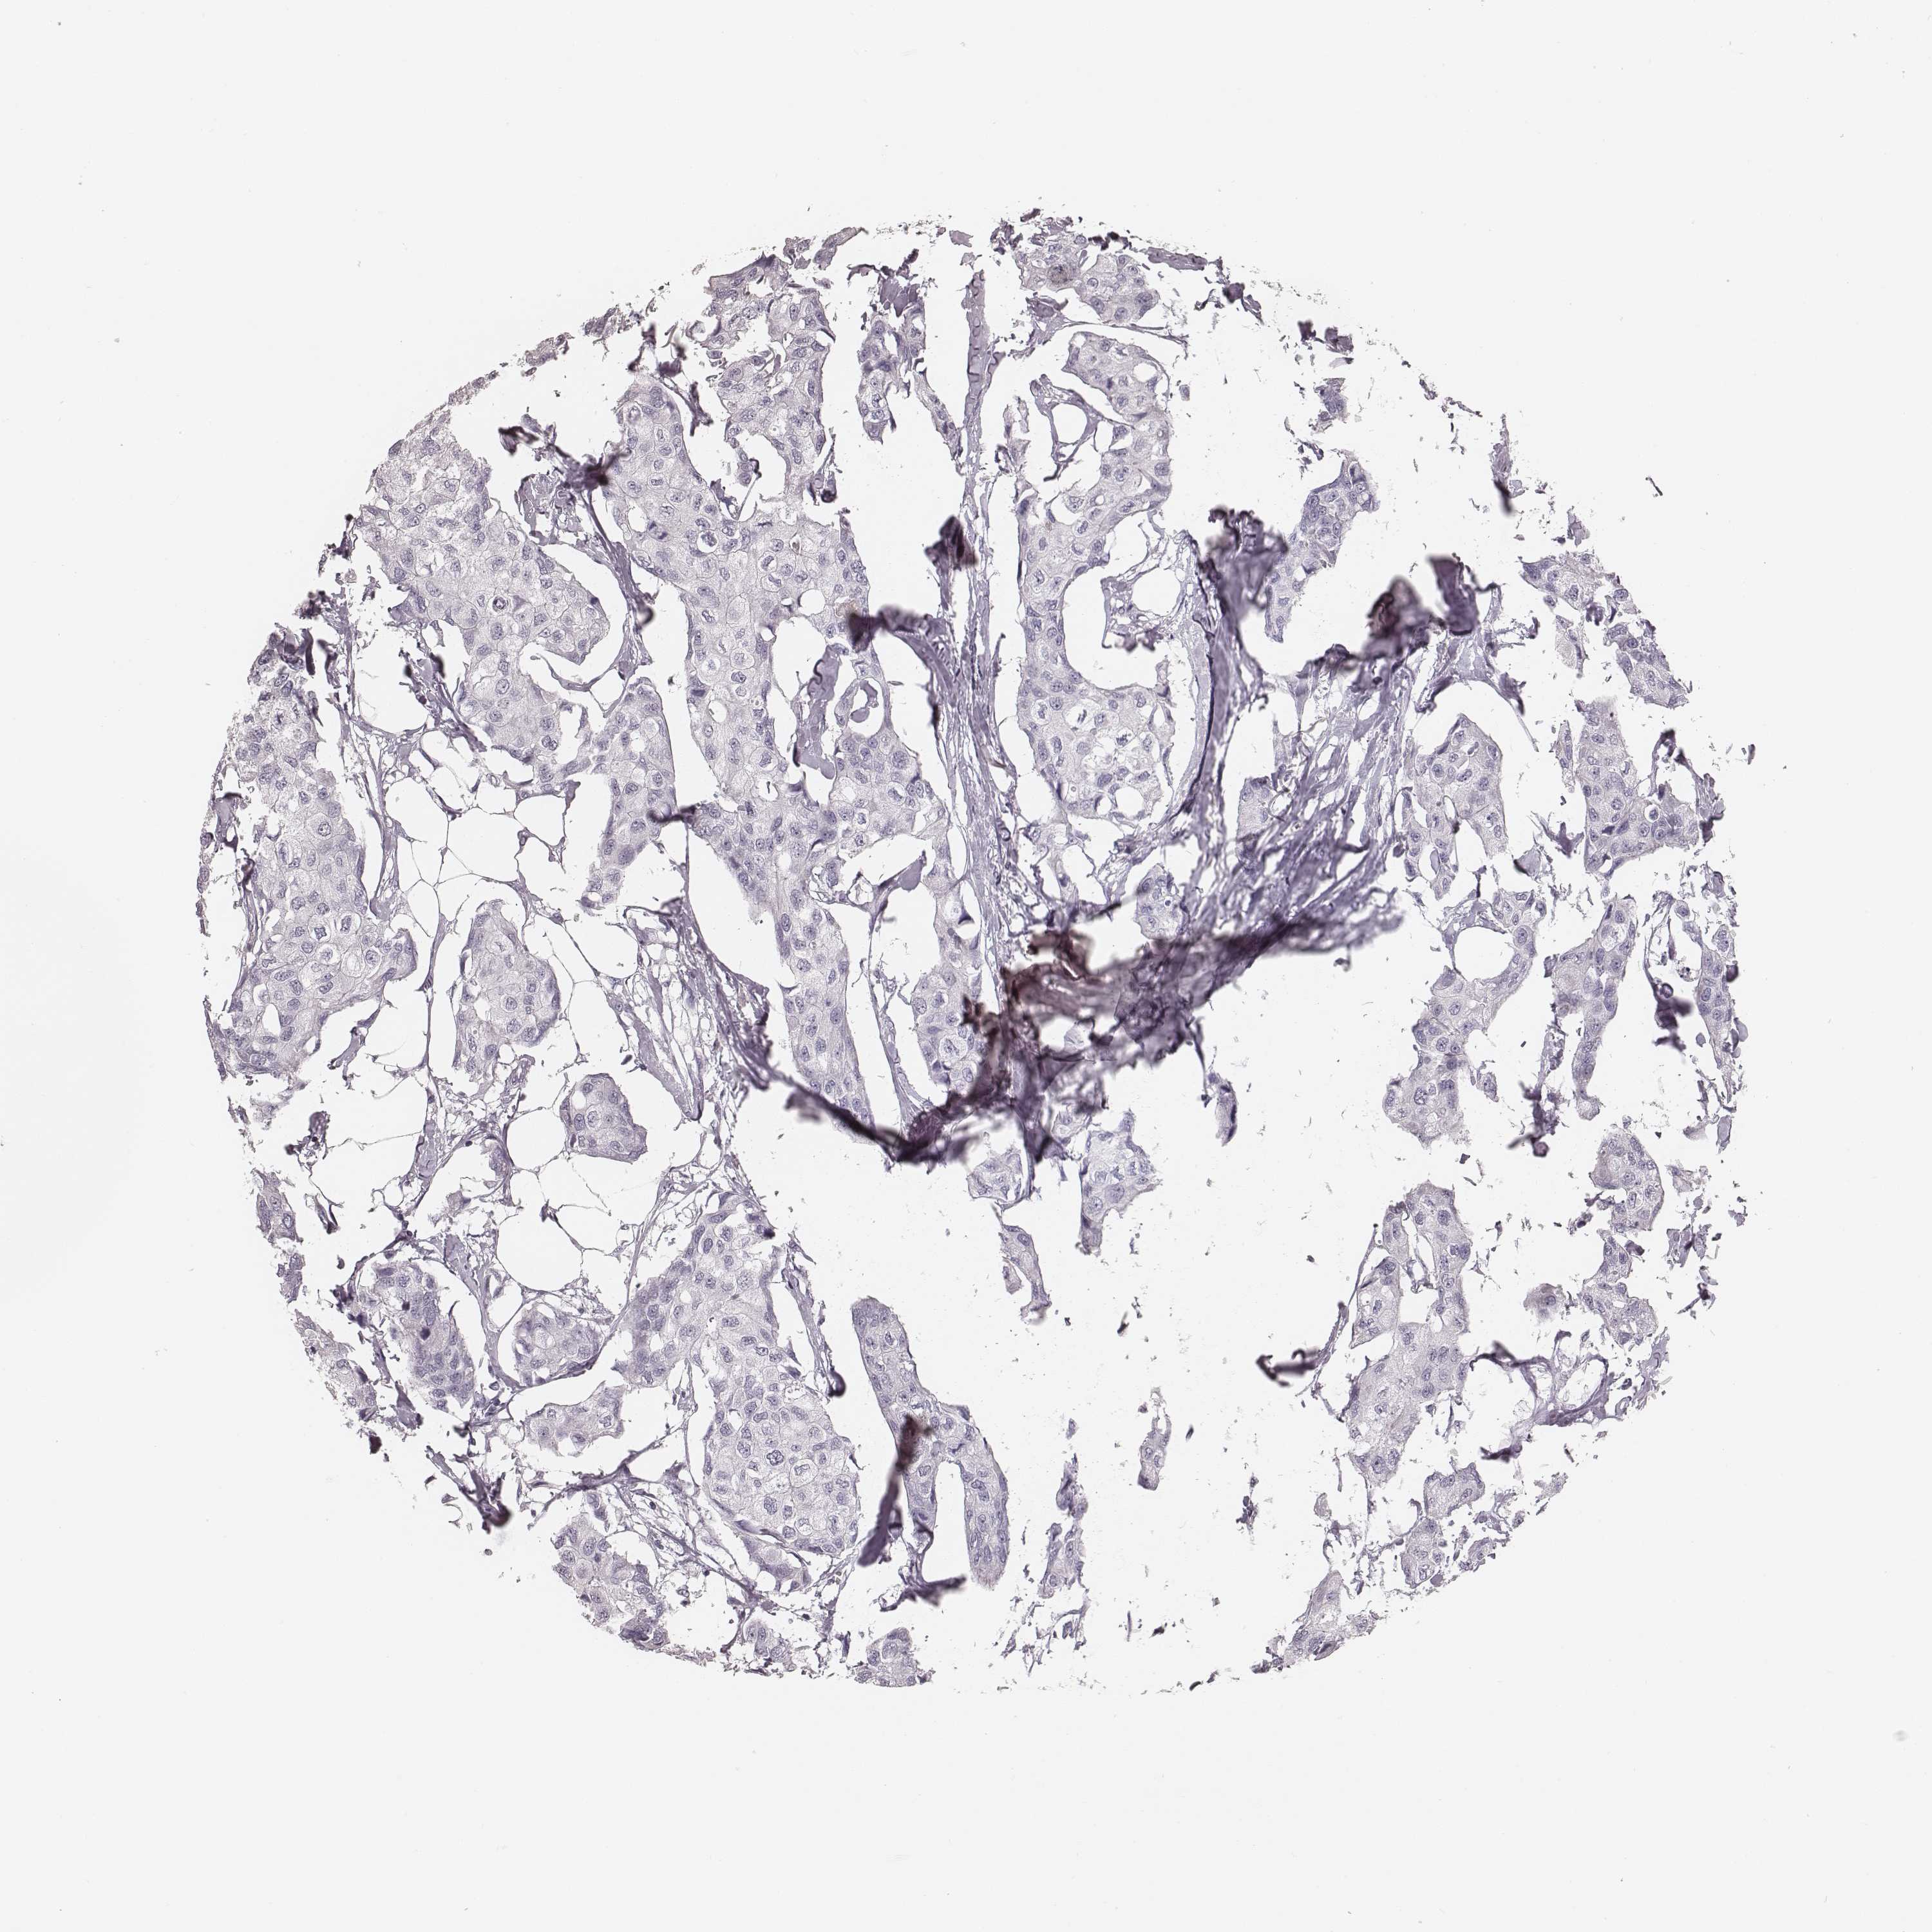

BRCA TCGA BRCA VALIDATION PROTEIN EXPRESSION

ANTIBODIES

AND

VALIDATION